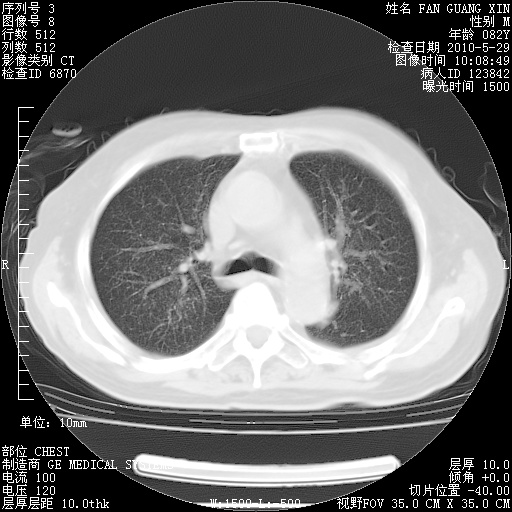

再治疗10天后的肺部CT

阅读此次胸部CT,肺间质渗出性改变较入院时有吸收。目前从体温、白细胞、中性分叶明显增高,肯定存在细菌感染(发生医院感染哦,若无消化道及泌尿系统等感染的依据,肺部感染可能大)。若你院头孢哌酮舒巴坦钠耐药率较高,同意你的方案,若48小时体温仍高,可考虑使用碳青霉稀类抗菌药物,同时可予超声雾化、注意滴数时加大液体量。白蛋白33.30g/L较低哦,需加强营养等支持治疗。